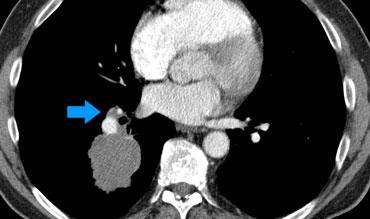

4. Ung thư dạng viêm phổi lan tỏa

- T3: Nếu khu trú trong cùng một thùy.

- T4: Nếu hiện diện cùng bên nhưng ở các thùy khác nhau.

- M1a: Nếu hiện diện ở thùy phổi đối bên.

- Một phân loại N và M duy nhất được áp dụng cho tất cả các tổn thương.

Ví dụ:

- T4N1M0, với phân loại T4 dựa trên tổn thương ở thùy dưới phổi phải (RLL).